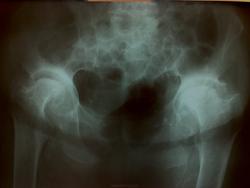

Ж., 80 лет, жалобы на боли в области правого т/б сустава после падения. Прошу прощения за укладку, ровнее не снять. Что с суставами?

Нужен анамнез, больше похоже на последствия болезни Пертеса

А может быть просто двухсторонний деформирующий коксартроз III ст.

".В тазобедренном суставе головка бедренной кости заметно уплощается и расширяется, иногда вдвое против нормы, принимая форму сдавленного гриба. Этому сопутствует утолщение шейки бедра за счет периостальных наслоений на ее внутренней поверхности. Одновременно уплощается и расширяется и вертлужная впадина. Обызвествление, а в дальнейшем и окостенение хрящевой губы вертлужной впадины углубляет суставную впадину и ограничивает движения в суставе ."http://www.radiomed.ru/publications/kss-artroz-rentgenologicheskaya-diagnostika-artroza

здесь нет выраженого сужения суставных щелей, справа так вообще расширена и при ДОА наверное были бы изменения структуры головки - остеосклероз, кистовидная перестройка, при ДОА головка деформируется не в такой степени, если там асептического некроза ( в смысле у взрослых) нет. Остеофиты здесь больше компенсаторные, вторичные

+yes. А почему не просто дисплазия, о которой никто и знал. Анамнез .

О дисплазии мысль была. Не исключено.

А почему головки так уменьшены, особенно правая?? Разве при ДОА такое бывает.... А по анамнезу - все что есть

в проекции шейки справа там есть крулглый дефект костной структуры,не может ли он давать боли.

...или асептического некроза головок, тут уж как нравится. В итоге исход в виде ДОА с формированием грибовидных головок.

На РА это больше похоже http://radiopaedia.org/cases/rheumatoid-arthritis-of-hip-with-erosion-and-pseudoarthrosis

Последствия болезни smiley. На мой взгляд, более вероятно. Ну или про дисплазию коллеги высказывались. Трясти амбулаторную карту, информацию из пациентки, маловероятно в 80 лет впервые выявленые такие изменени.

В этом случае наверное уже давно завершен.  Читал, что углубление вертлужных впадин может быть при воспалительных болезнях, но ведь нет сужения суставной щели, узурации.

- Наблюдается у детей чаще в возрасте от 4—5 до 11—14 лет. Мальчики болеют в 3—4 раза чаще девочек..... Преимущественно процесс односторонний.

- восстановительная фаза — рассасывание некротической ткани и восстановление костной структуры. На рентгенограммах почти всегда отмечается типичная деформация головки и шейки бедра. Головка принимает грибовидную форму. Шейка укорачивается, шеечно-диафизарный угол уменьшается. Вертлужная впадина уплощается. Расширена рентгеновская суставная щель, сохраняется подвывих бедра кнаружи.